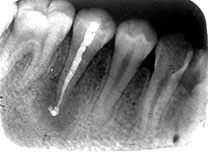

根尖周围炎是局限于牙齿根尖组织的炎症过程。大多数是由于牙髓坏死或坏疽发展而引起,少数病例是由牙体外伤或牙周感染引起。本病临床上分为急性和慢性两种,在急性期末及时治疗可形成牙槽脓肿。